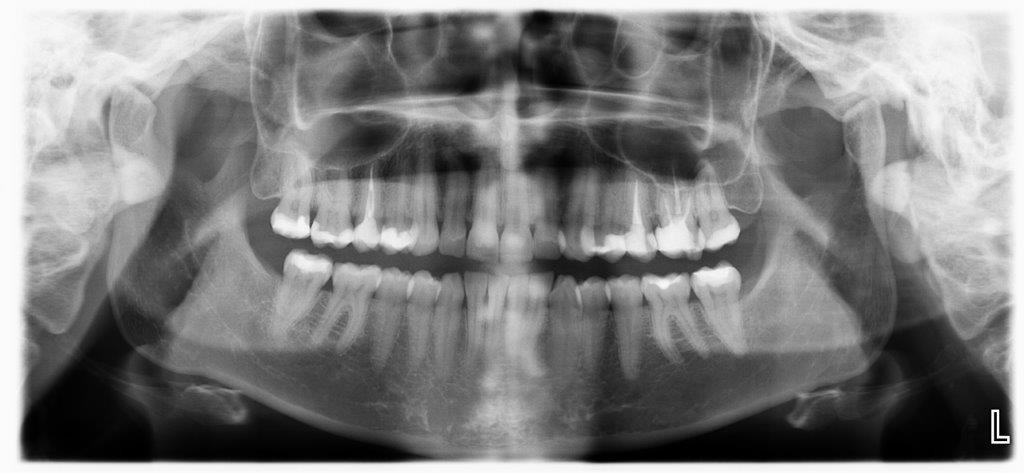

eine adhesivbrücke ist bei knirschern / pressern kontraindiziert. die ankerzähne werden mehr belastet, besser wäre eine normale brücke und vermutlich noch besser, ein zahnimplantat, denn so verlagert man den kaudruck auf mehr “pfeiler”. wenn du mir ein aktuelles panormaröntgen hochladest, kann ich dir mehr sagen.

Das ist ja nicht so toll ich habe auch das Gefühl ich knirschen viel auf der Brücke und dem nebenliegenden Zahn. Die Brücke ist auch schon einmal abgebrochen vor kurzem und wurde wieder befestigt. Ich habe leider nur ein Röntgenbild auf dem der 1,4 noch drin ist und der 1,7 noch nicht Wurzelbehandelt aber vlt können Sie trotzdem etwas bezüglich des kiefer sehen. Danach war ich schwanger und man konnte bis jetzt kein Bild mehr machen was aktuell ist. Wie kann ich das den hier überhaupt mit abhängen oder per Mail?